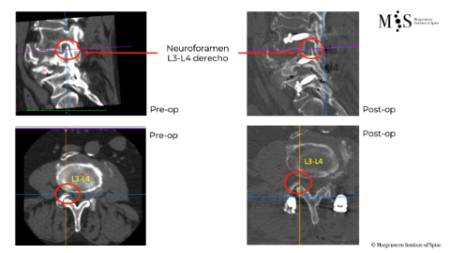

Clinical case example of a lumbar vertebral body resection (corpectomy) and reconstruction of a burst fracture at level L4.

Vertebral body resection (corpectomy) and reconstruction of complex vertebral and burst fractures

Severe vertebral body fractures, i.e. conminute and burst fractures, may require a partial vertebral body resection (corpectomy) and reconstruction with an expandable vertebral body cage. Especially severe fracture cases are also those with a bone fragment moving into the spinal canal that compresses on neural structures, such as the spinal cord and causes spinal canal stenosis. Corpectomy allows to resect most of the fractured body, including the bone fragments pushing on the nerves and intruding into the spinal canal. The vertebral body reconstruction is usually rounded up with a posterior augmented instrumented fusion of the adjacent levels to the fracture. All of this allows a proper healing of the fracture and the patient to recover without pain.